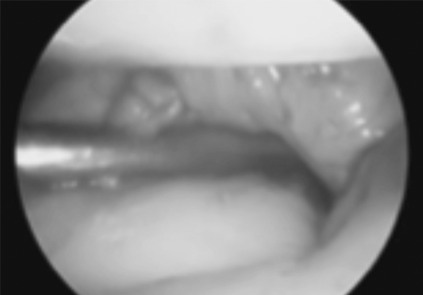

L’engruiximent i la constricció de la beina sinovial impedeix el lliscament fàcil dels tendons que flexionen els dits.

Aquesta malaltia es caracteritza per una contractura de la palma i dits de la mà deguda a una proliferació del col·lagen.